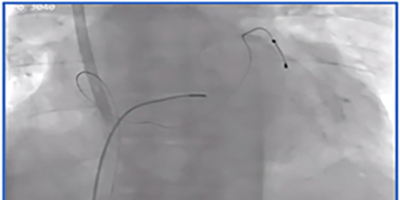

Ablation of Idiopathic Premature Ventricular Arrhythmias Originating from the Basal Cardiac Crux Region: A Case Report

See Videos